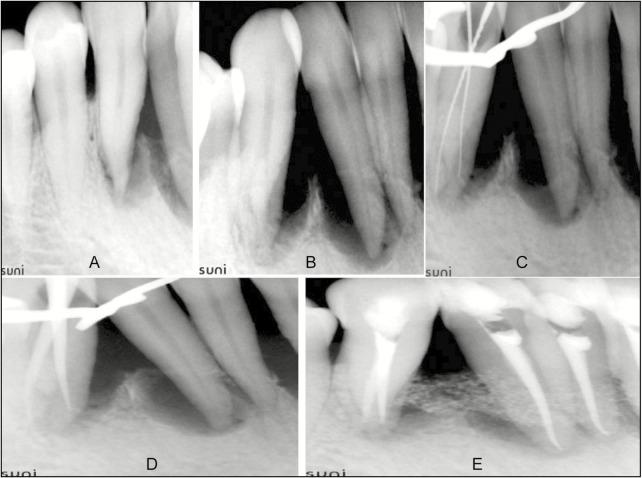

It is very rare (2%-6% cases) for a mandibular canine to have two root canals and the incidence of finding two roots with two root canals in a mandibular canine that too bilaterally is almost negligible. This case report discusses the presence and multidisciplinary management of such rarest configuration in both mandibular canines of a female patient. This case shows the importance of recognition of anatomical variations in successful accomplishment of root canal treatment.